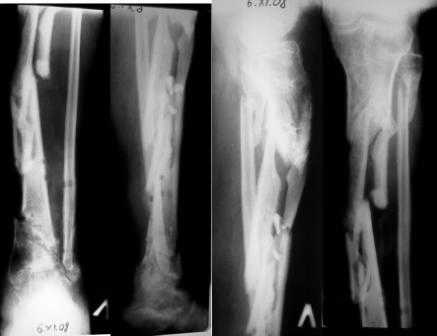

Больной К 45 лет, ДЗ: ложный сустав левой голени. Травма 1 год назад, ТСТ. открытый фрагментарный перелом левой голени, перелом мыщелков левой голени, н.з малоберцовой кости. +плечо, Алкогольный делирий. В настоящий момент левая нижняя конечность не опорная, имеется патологическая подвижность в с.з голени. Раны зажили более 6 мес назад.

Нашпиговать на гвоздь как на “шашлычную палочку” остаток большеберцой кости до тарана не составляет трудности, (на снимке голеностопный сустав безнадежно потерян) но для такой операции нужны специальные сверла. (др.Челноков показывал “custom made” сверла)

В подобной ситуации мы, очевидно, использовали бы перемещение нерасщепленной малоберцовой кости. Техника достаточно проста: двойная остеотомия fibula, ее дозированное (1-3 мм/сут) перемещение спицами с упорами. Для обеспечения лучших условий сращения целесообразно выполнить открытую адаптацию на каждом из концов перемещенного малоберцового фрагмента. Пример прилагается.